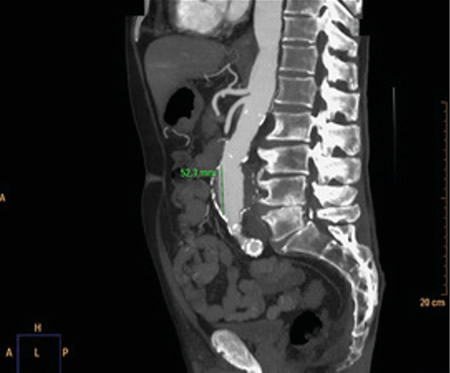

Respecto a las pruebas complementarias, en la analítica sanguínea, se halla una PCR de 39,1 mg/l, leucocitosis de 21.300/mm3, con 88 % de neutrófilos, y una hemoglobina de 10,5 g/dl. En la radiografía pélvica no se evidencian hallazgos patológicos. Debido a la hipotensión, se decide realizar un TC abdominal (Figuras 1 y 2), en el que se objetiva un aneurisma de aorta infrarrenal roto, con diámetro de 50 x 52 x 48 milímetros, a 50 mm de arteria renal derecha y a 65 mm de arteria renal izquierda, craneal a la bifurcación ilíaca. Asimismo, se aprecia un hematoma retroperitoneal en contexto de sangrado en parte posterior de la aorta, que infiltra el músculo psoas ilíaco izquierdo, justificando la clínica de coxalgia con irradiación izquierda. Se contacta con cirugía vascular, interviniéndose de forma urgente, con buena evolución posterior.

Fig. 1. TC coronal de aneurisma de aorta abdominal.